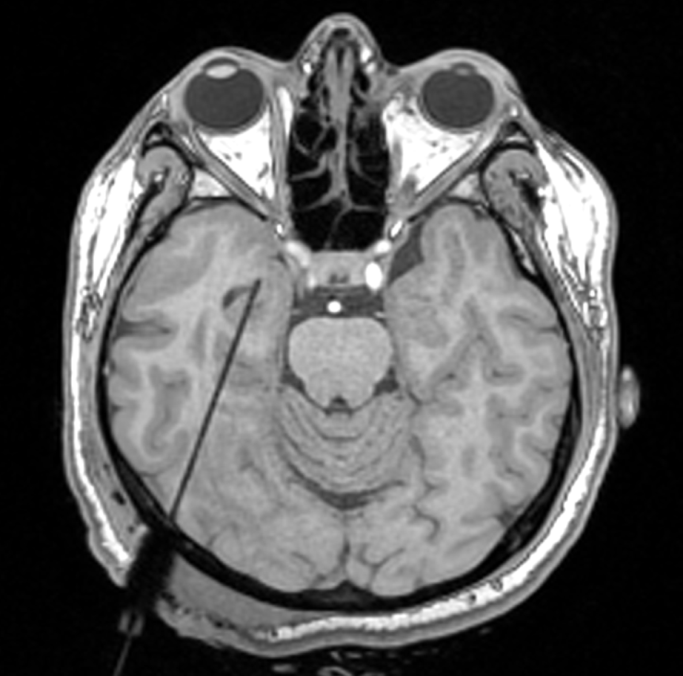

— chirurgiczne leczenie padaczki z uwzględnieniem technik ablacji obszaru padaczkorodnego